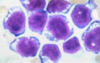

¿Cómo es la célula de Reed-Sternberg clásica?

Célula grande binucleada con nucléolos prominentes en ojos de búho.

¿Cuál es la célula neoplásica del linfoma de Hodgkin?

Célula de Hodgkin/Reed-Sternberg.